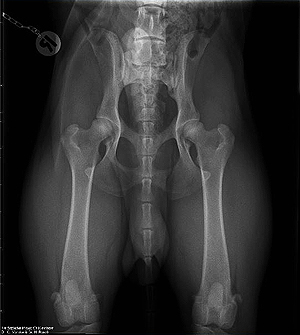

Die ersten drei Röntgenergebnisse von

Hunden aus meinem Q-ll-Wurf liegen vor:

Q ex Chelsea: HD: A 2 / B 2 ED: 0/0, LÜW: 0

Quincy ex Chelsea: HD: A1 / A1,

ED-Grad: 0 / 0, LÜW: 0 Quitman ex Chelsea: HD: A2 / A2,

ED-Grad: 0 / 0, LÜW: 0

(Francolino ex Chelsea x Colby ex Chelsea)

Geröntgt wurden die Hunde in den Vet.-Med.-Unikliniken in

Giessen und Leipzig: Wie immer perfekt angefertigte Röntgenaufnahmen =

beste Adressen!

HD-Rö.-Aufnahme: Quitman ex Chelsea